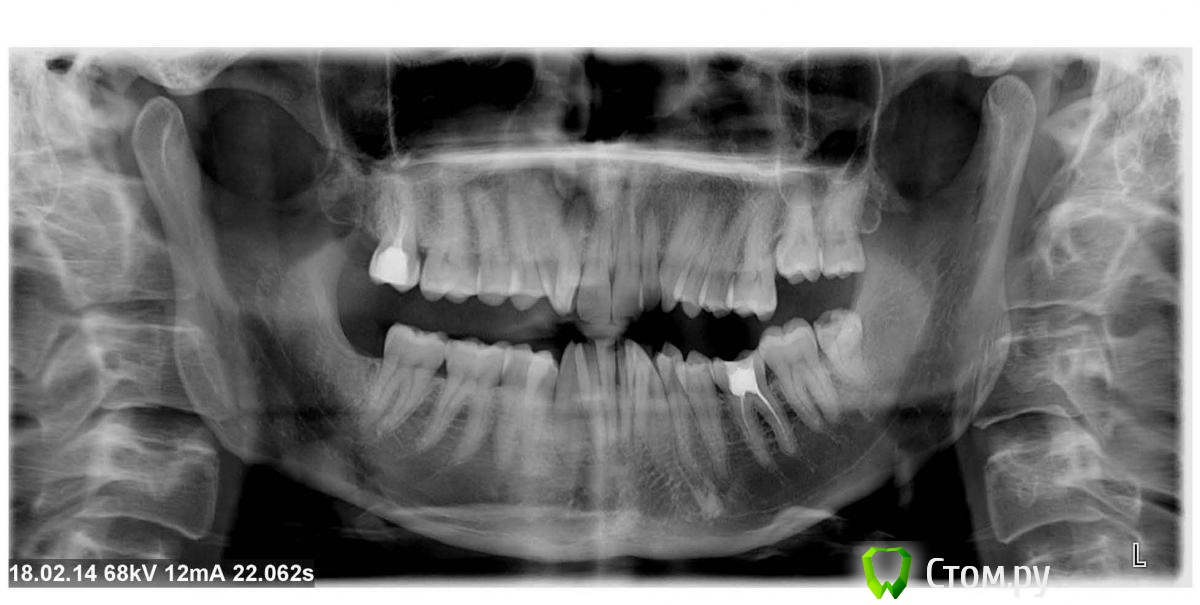

Анатолий М Опубликовано 21 апреля, 2014 Поделиться Опубликовано 21 апреля, 2014 Добрый день. Помогите пожалуйста.17 зуб (верхняя семерка с права). Пол года назад был депульпирован. Все это время присутствуют боли под этим зубом по симптомам очень похожие на кисту (распирание, боль ноющая не сильная, то появляется то сама собой изчезает. при перкуссии 17 зуб слегка болезненный). 2 месяца наза решили зуб перелечить. На ОПТГ ситуация до перелечивания. По снимку видно что первоначальное лечение было проведено плохо. Корни были плохо пройдены и плохо заполены цементом.Месяц хождения с гидроокисью кальция на воде никакого эфекта не дали. Врачи считают что под зубом есть киста. И предлагают удалить зуб. Так как перелечивание не помогло.Прилагаю снимок КЛКТ после лечения. Зуб все еще под временной пломбой. Из трех врачей лишь один разгледел на КЛКТ кисту под 17 зубом. Два других ни на КЛКТ ни на прицельных никакой кисты не видят. Направили к неврологу. Думают что киста если она и есть (в чем они не уверены) не дает имеющихся симптомов.Пожалуйста посмотрите на КЛКТ. Есть ли там киста или нет? И могут ли боли быть от нее?Заранее спасибо. Ссылка на комментарий

Анатолий М Опубликовано 21 апреля, 2014 Автор Поделиться Опубликовано 21 апреля, 2014 КТ до лечения. Эту пломбу вскрыли. Каналы полностью проработали и поставили лекарство. 3 раза меняли по принципу 3дня+3нед+4недели. Ниже приложен КТ контрольный через месяц лечения. Сейчас в каналах лекарство. Кт после постоянного пломбирования корневых каналов? Есть снимки во время лечения и контрольный после? Ссылка на комментарий

Анатолий М Опубликовано 21 апреля, 2014 Автор Поделиться Опубликовано 21 апреля, 2014 Снимок во время лечения делали? Коффердам и оптика использовались? На кт в тех срезах что Вы выложили кисты не вижу Снимки во время лечения делали три раза прицельные с иголками в каналах. Но они остались у врача. У меня их нет. Но она по ним кисты не видела. Коффердам использовали только при первом посещении когда вскрывали старую пломбу и прорабатывали каналы. При последующих посещениях при смене лекарст его не использовали так как кольцо на зубе плохо держалось и постоянно слетало. Плюс травмировало десну.Микроскоп использовали все три раза. По словам врача (врач высшей категории эндодонтист зав отделением):При вскрытии старой пломбы каналы практически не заполены цементирующим составом. Иструмент при вскрытии пломбы в каналы проваливался. Хотя стояла постоянна пломба. Из трех каналов лишь один был проработан до верхушки корня. Два других либо до половины либо на треть. Врачь полностью прошла все каналы и даже залезла за апекс. туда при первом пломбировании врач даже не пыталась лезть. При третьем посещении врач констатировала что каналы чистые. Никаких признаков инфекции нет. И белезненная перкуссия от чего то другого. Специально проводила ревизию каналов при втором и третьем посещении без анастезии что бы понять где болит. Но так и не поняла. Повела на консультацию к профессору в их стоматологи. Посмотрев контрольную КТ он сказал что там киста и надо удалять зуб! Похоже что мой врач с ним не очень согласна, хотя и спорить не стала поэтому отправила меня на консультацию к неврологу. Ниже срезы конрольного КТ после месяца лечения гидрооксидом кальция на воде. Срезы по дуге. Сделал как смог. Шаг срезов как я понимаю 1мм. Линия по перек дуги снимок номер 1 (см нумерацию в конце названия файла) Ссылка на комментарий

igorstom Опубликовано 26 апреля, 2014 Поделиться Опубликовано 26 апреля, 2014 (изменено) Понятие кисты двоякое. Кистой можно назвать полостное образование размером на рентгеновском снимке более 8 мм в диаметре. Ну а есть понятие гистологическое. Тут размер не имеет значения. А результаты гистологического исследования - эпителиальная выстилка и клеточные элементы. В практике, по крайней мере у нас на Урале доктора часто "кистами" называют даже незначительные округлые элементы на верхушках корней. Так что причин на мой взгляд для беспокойства нет. А вот пустота каналов лично меня насторожила бы. Гидроокись кальция всё-таки рентгеноконтрастна, хоть и незначительно. Но и этого я не увидел на снимках. Но это только моё вИдение. Изменено 26 апреля, 2014 пользователем igorstom 1 Ссылка на комментарий